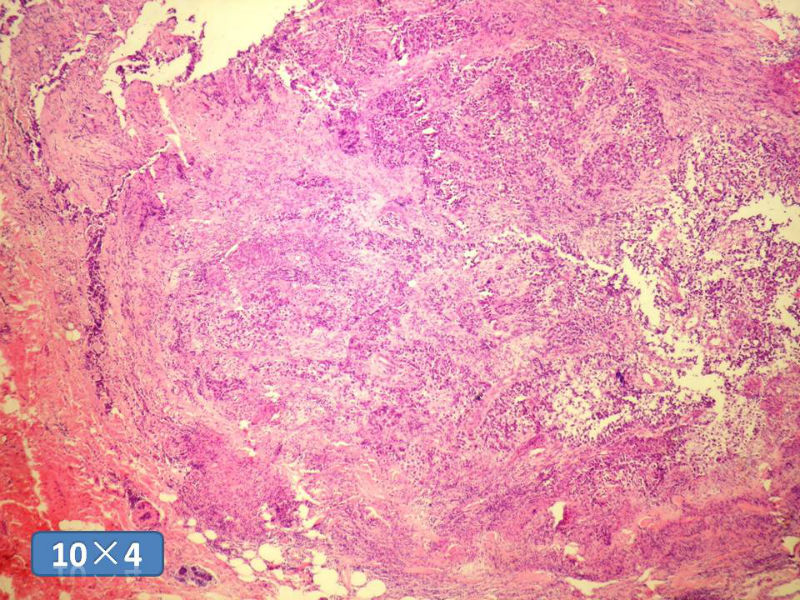

女性,50岁,乳腺肿物,冰冻切片(图1-25)

HE

DCIS LCIS IDC